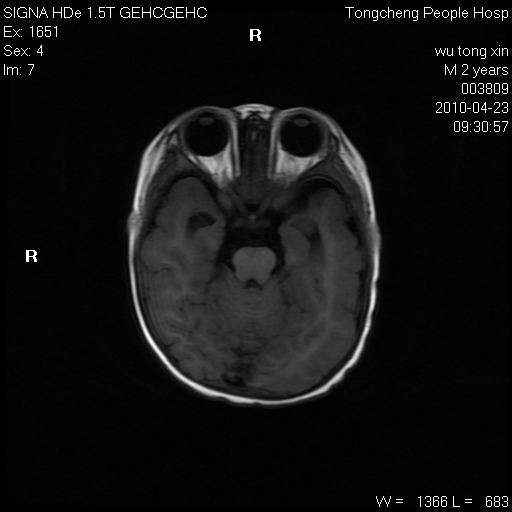

以下是引用赵物学在2010-4-25 12:43:00的发言:[br]巨脑回[br]侧脑室后角低密度影考虑hie或肾上腺脑白质营养不良?[br][br][本贴已被 赵物学 于 2010-4-25 12:51:28 修改过]

以下是引用gaoxiao在2010-4-25 16:54:00的发言:[br]巨脑回畸形。脑白质髓鞘化不良

以下是引用pujunzhi在2010-4-25 21:35:00的发言:[br]考虑 1双侧大脑皮质发育不良 2轻度脑积水 3双侧脑室后角旁片状长t1长t2信号,需继续观察,因为正常小儿此处脑白质的髓鞘化时间可以延迟到4-6岁,才显示正常。